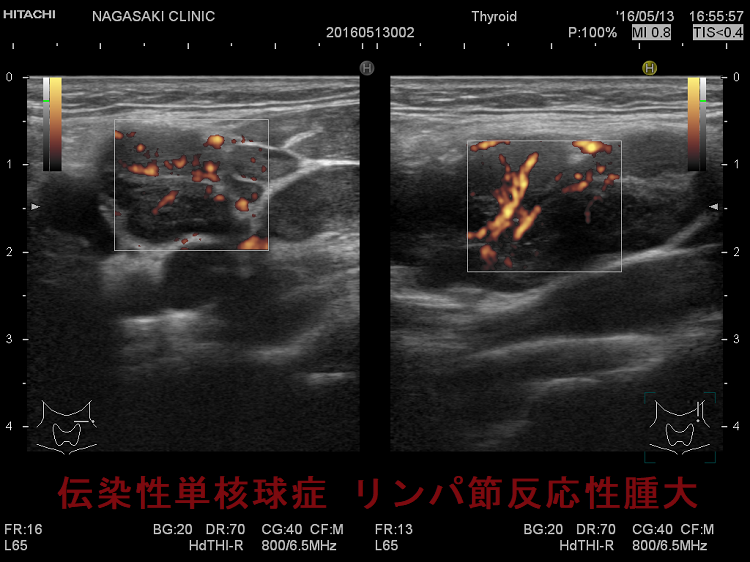

亜急性甲状腺炎と鑑別を要する伝染性単核球症。喉(のど)の痛みと首のリンパ節の腫れを甲状腺の病気と思って、長崎甲状腺クリニック(大阪)を受診される方がおられます。

- 痛みを伴う著明な後頸部リンパ節腫脹は1〜2週頃がピークで、耳下腺の下、外側頚部まで累々と広がり、全身のリンパ節も腫大します。

- 亜急性甲状腺炎と鑑別を要する伝染性単核球症を発症